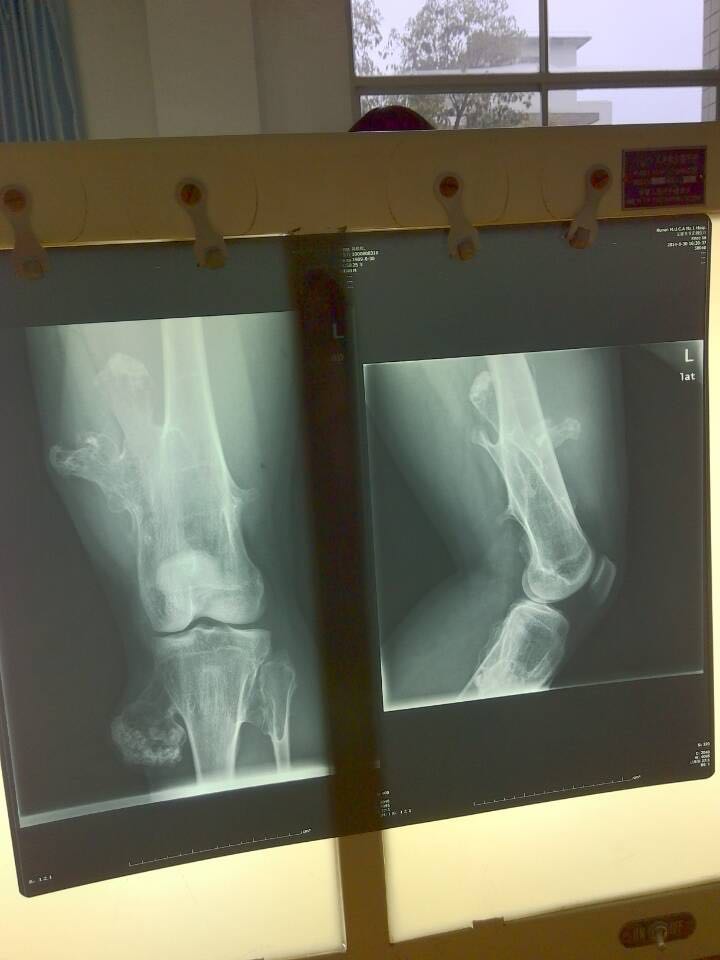

男 9岁,发现左跟骨肿物半年余,行走后疼痛不适,诊断为左跟骨骨软骨瘤,建议手术治疗。 病史1年前有轻微外伤史,未做特殊处理,半年前左跟骨底出现一硬物,行走后疼痛加重,无夜间痛。 左跟骨未见明显红肿,皮温不高,可触及骨性突起,呈卵圆形,质硬,边界清晰,推之不移,有压痛,足踝关节活动功能未见明显异常,神经感觉功能活动正常。 图1 左跟骨侧位可见跟骨底骨骺下方帽状骨性组织图2右足跟骨侧位为正常骨组织图3 左跟骨CT 三维重建示:右跟骨底骨骺下方凸起帽状组织。 CT三维重建示:左足跟部可见一扁平帽状骨化,约1.0cm×2.6cm大小,左跟骨结节骨骺核较对侧扁平,密度不均,部分骺线变窄甚至消失,左足跟骨后部可见片状骨质硬化,边缘模糊(图3)。MRI示左侧跟骨后份见不规则长T1短T2信号,跟骨结节骨骺扁平似碎裂,信号欠均匀,骺线信号尚可,其右下方见一不规则长T1短T2信号,SPAIR像为略高信号,大小为2.8cm×1.3cm,边界清晰,跟腱形态、信号未见明显异常。 诊断:左跟骨骨软骨瘤 治疗:手术在硬膜外加局部麻醉下行左跟骨骨软骨瘤切除术,取左跟骨内侧长约7cm切口,分离各组织,然后显露跟骨底部骨性突起部分,大小约为4cm×2cm×1cm,通过C型臂透视机透视下克氏针定位肿物边界,然后将肿物全部切除,肿物未见头帽状凸起,呈松质骨样。病理诊断为左跟骨骨软骨瘤。患肢功能感觉及血运未见明显异常。